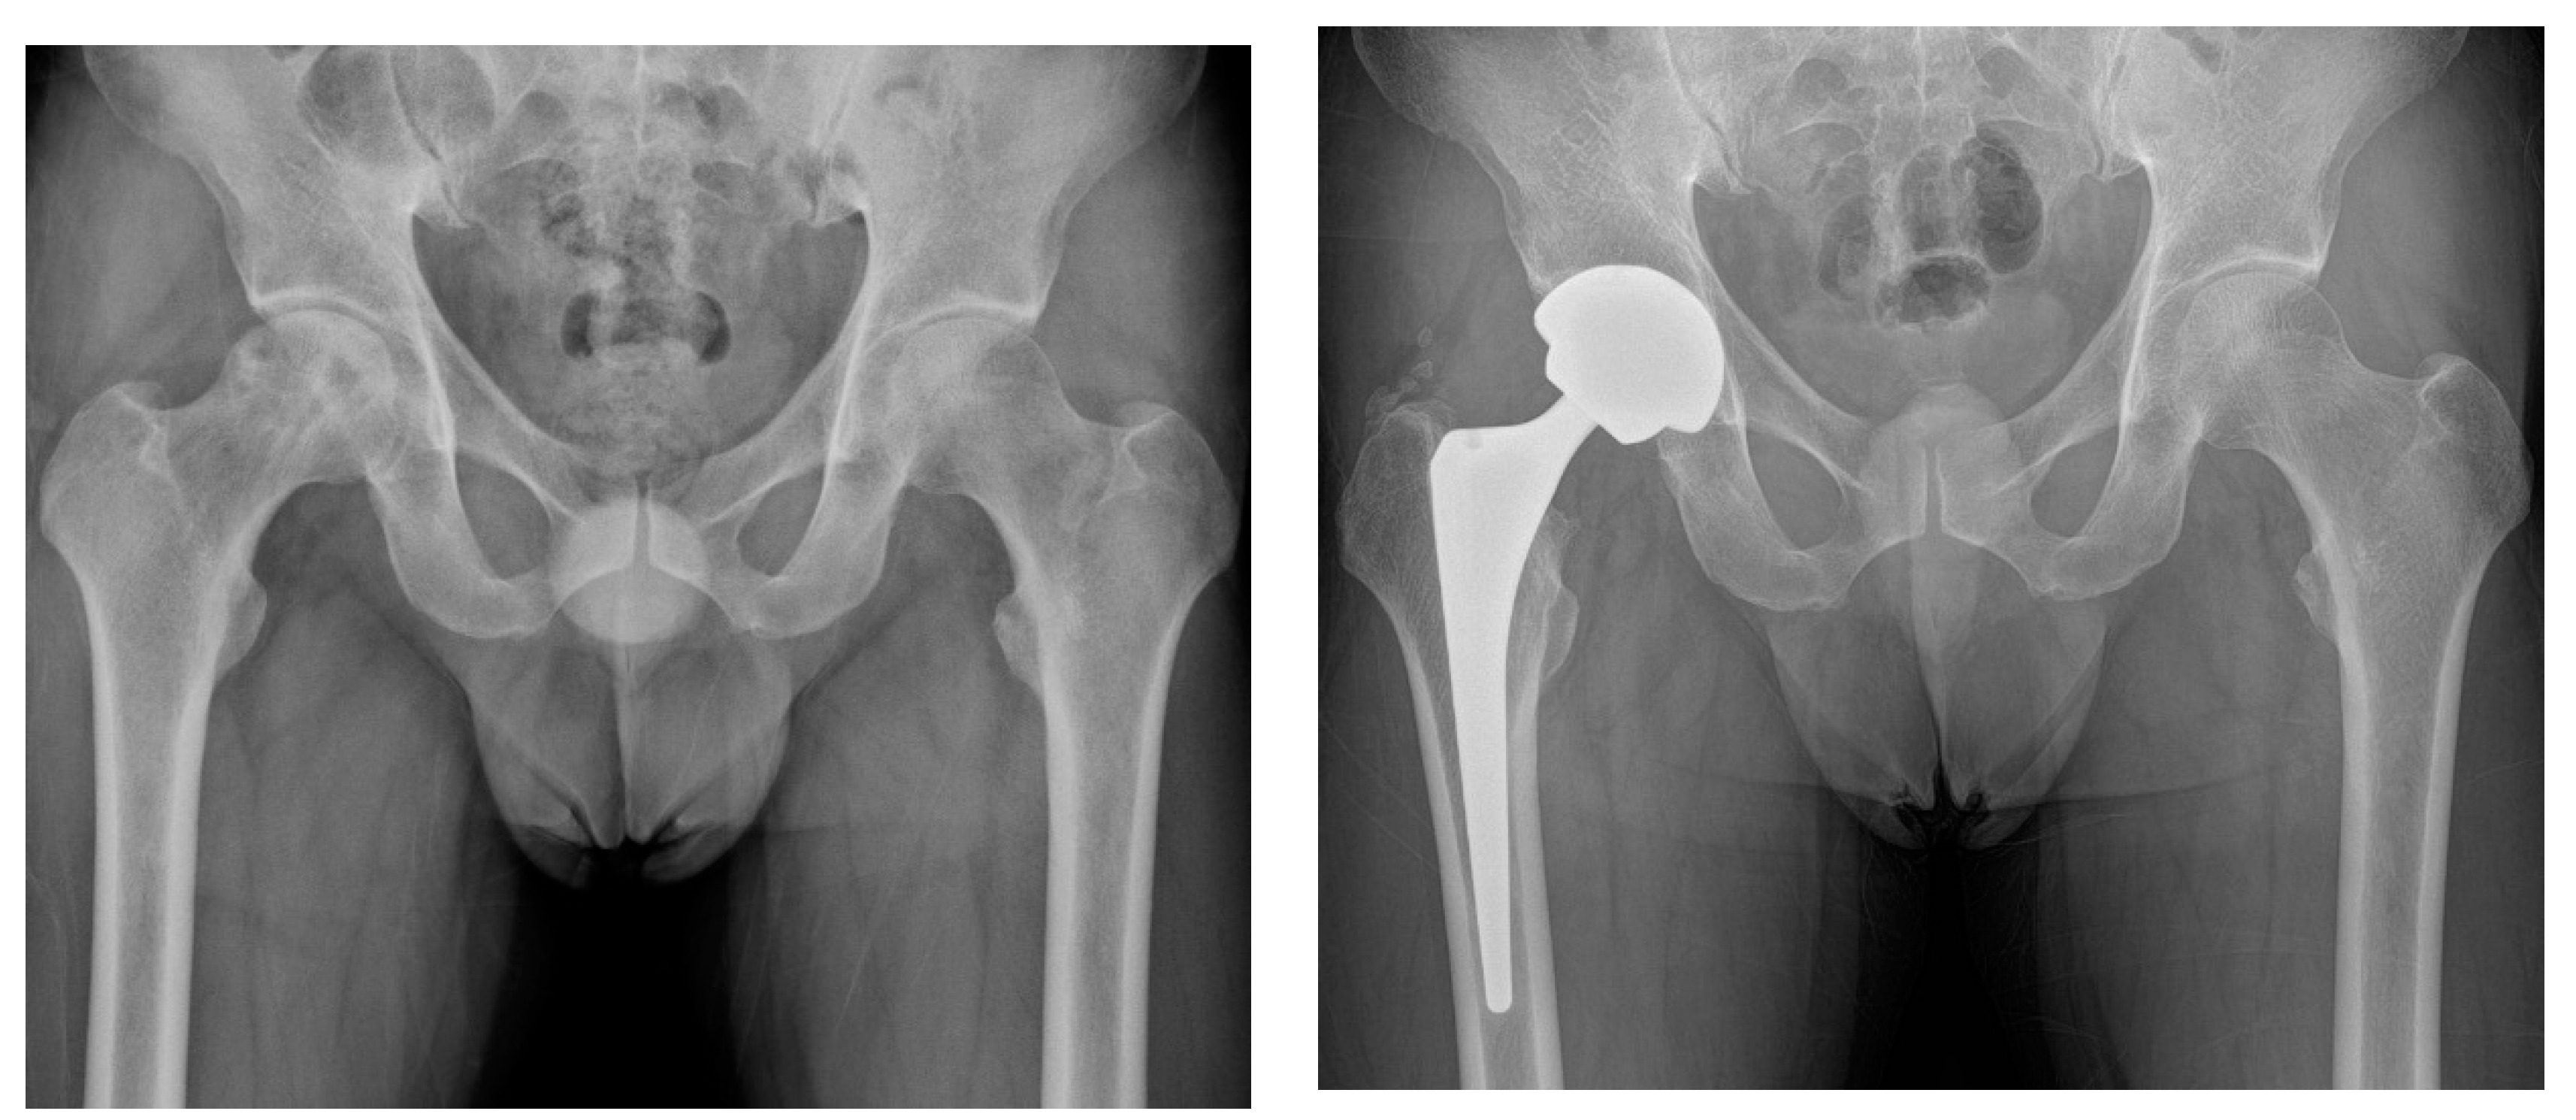

Figure 2.

(A,B) Preoperative and postoperative hip radiographs of a 33-year-old woman with cognitive dysfunction and visual disturbance after removal of recurrent craniopharyngioma. She underwent simultaneous bilateral THA due to ONFH. (C,D) Radiographs of the same woman on the 15th postoperative day, when she visited the emergency department due to severe pain in the left hip. Anteroposterior and lateral images demonstrated anterior hip dislocation. (E) Hip radiograph after performing closed reduction followed by abduction brace application under general anesthesia. (F) Eight-year postoperative radiograph showed stable implant fixations.